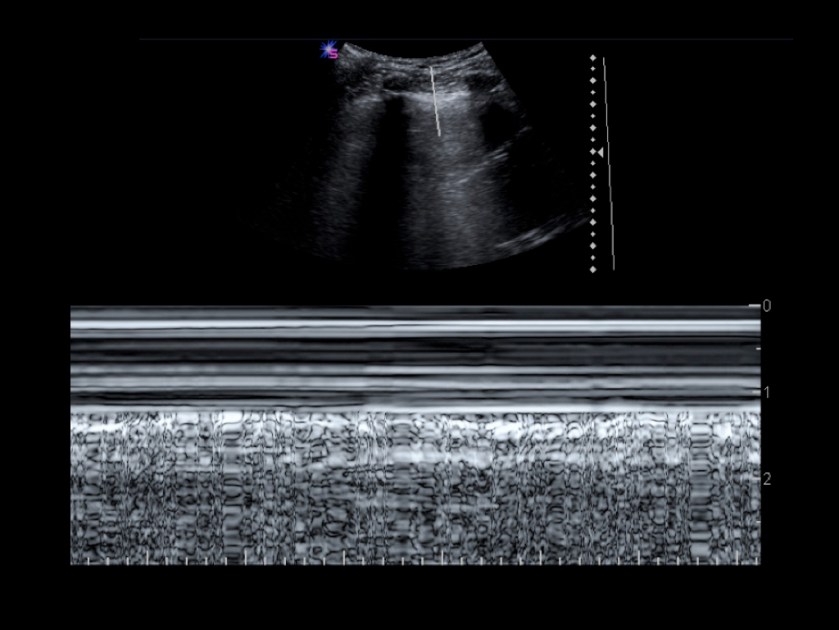

Der Lungenpunkt stellt die Grenze zwischen der Thoraxwand anliegender Lunge und Beginn des Pneumothorax dar. Mit Anwesenheit dieses Zeichens ist ein Pneumothorax mit nahezu hundertprozentiger Sicherheit bewiesen.